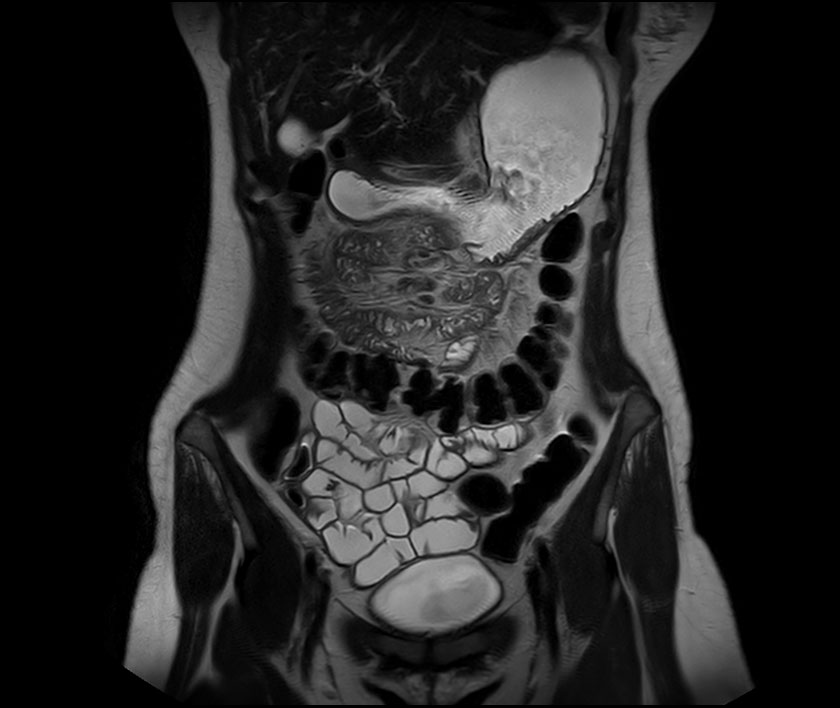

Small intestine in Crohn's disease, MRI Stock Image C029/4649 Can An Mri Scan Detect Crohn Disease In addition, mri enterography and enteroclysis has allowed detection of small bowel crohn disease, similar to that of small bowel series, with the additional benefits of. These tests check for signs of infection, inflammation, internal bleeding, and low levels of substances such as iron, protein, or. New and emerging roles of mri in inflammatory bowel disease. There’s no single diagnostic. Can An Mri Scan Detect Crohn Disease.